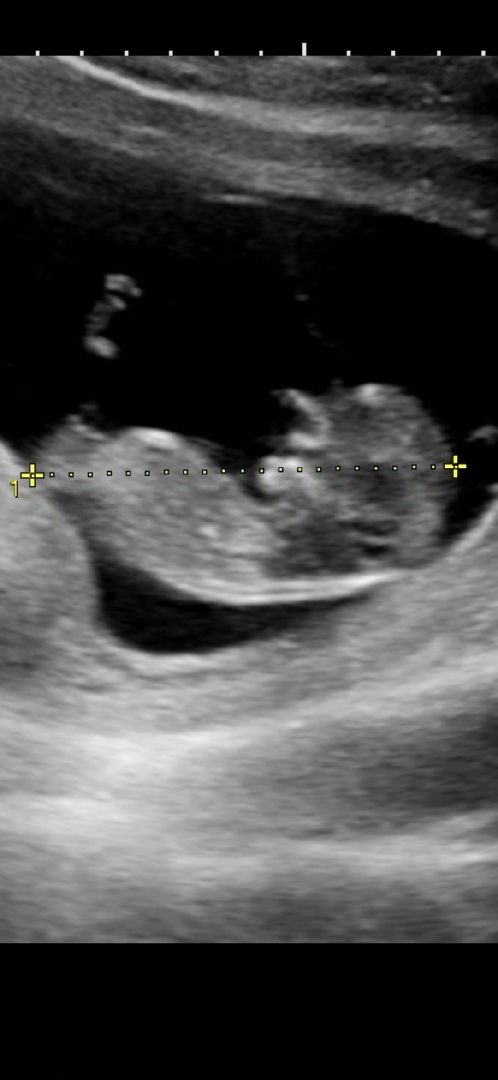

11주4일 각도법 의견한마디씩 부탁드려요

잘 보시는 고수님들 의견부탁드립니다! 기다리면 알수있겠지만 궁금한건 어쩔수없네요 ㅎㅎㅎ